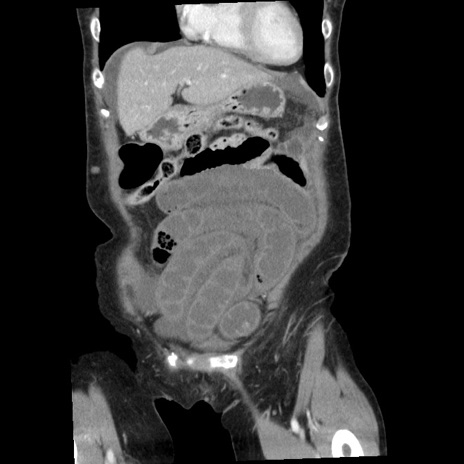

横断像

【症例】80歳代女性

【主訴】腹痛

【現病歴】8時間前から腹痛あり来院。

【既往歴】糖尿病、脂質異常症、子宮体癌にて子宮全摘術

【身体所見】意識清明・会話良好だが腹痛で苦悶様、全腹部にわたって反跳痛と圧痛あり

【データ】WBC 13600、CRP 0.14、LDH 224、CK 90